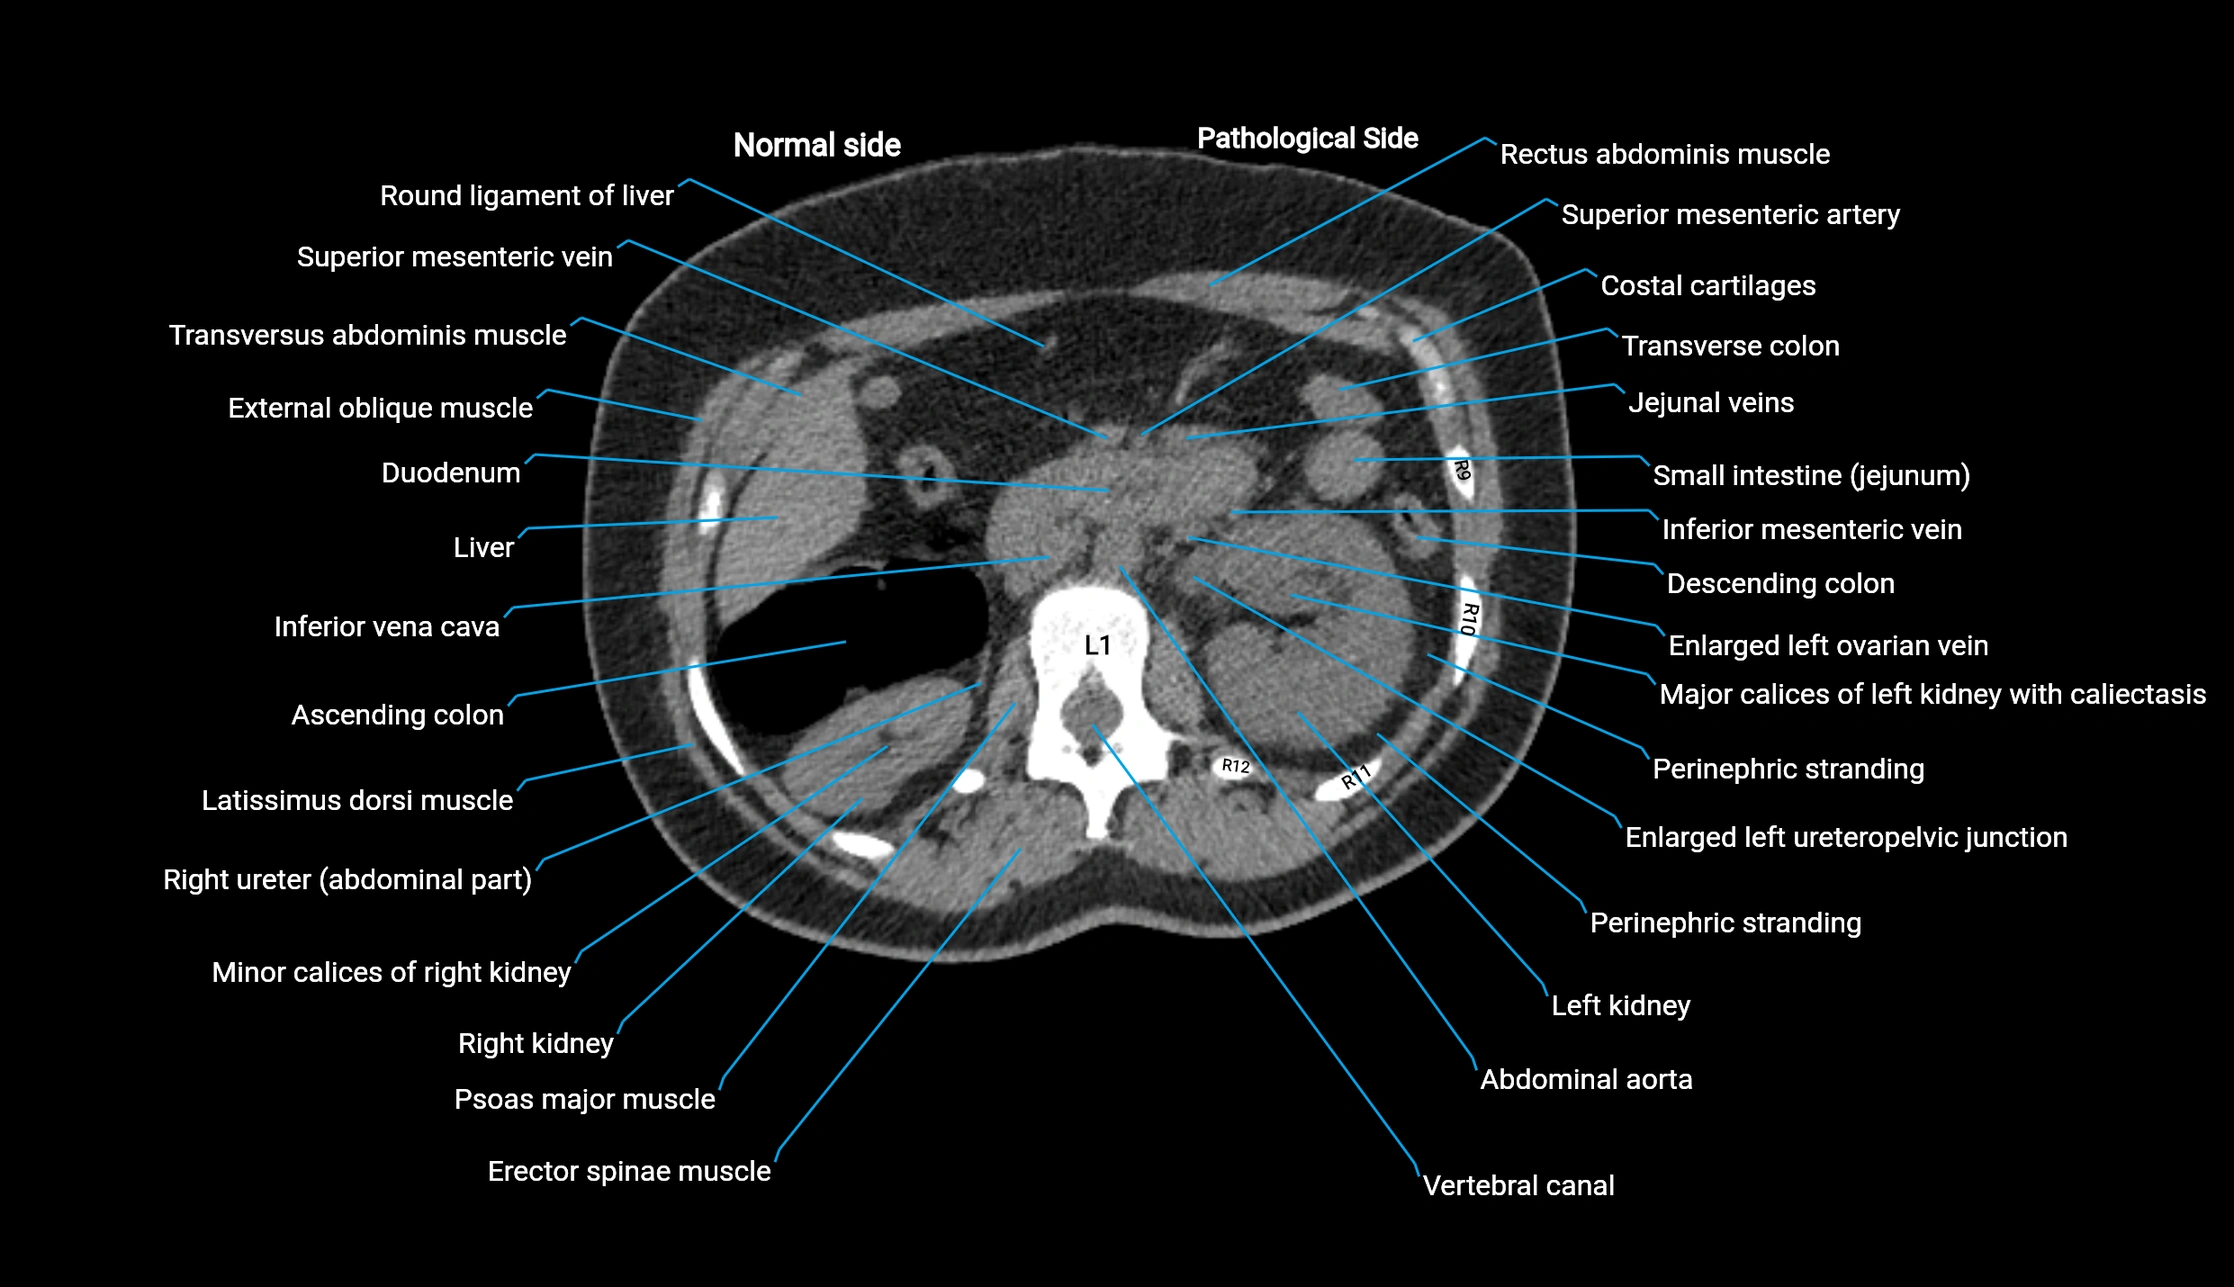

CT image

image